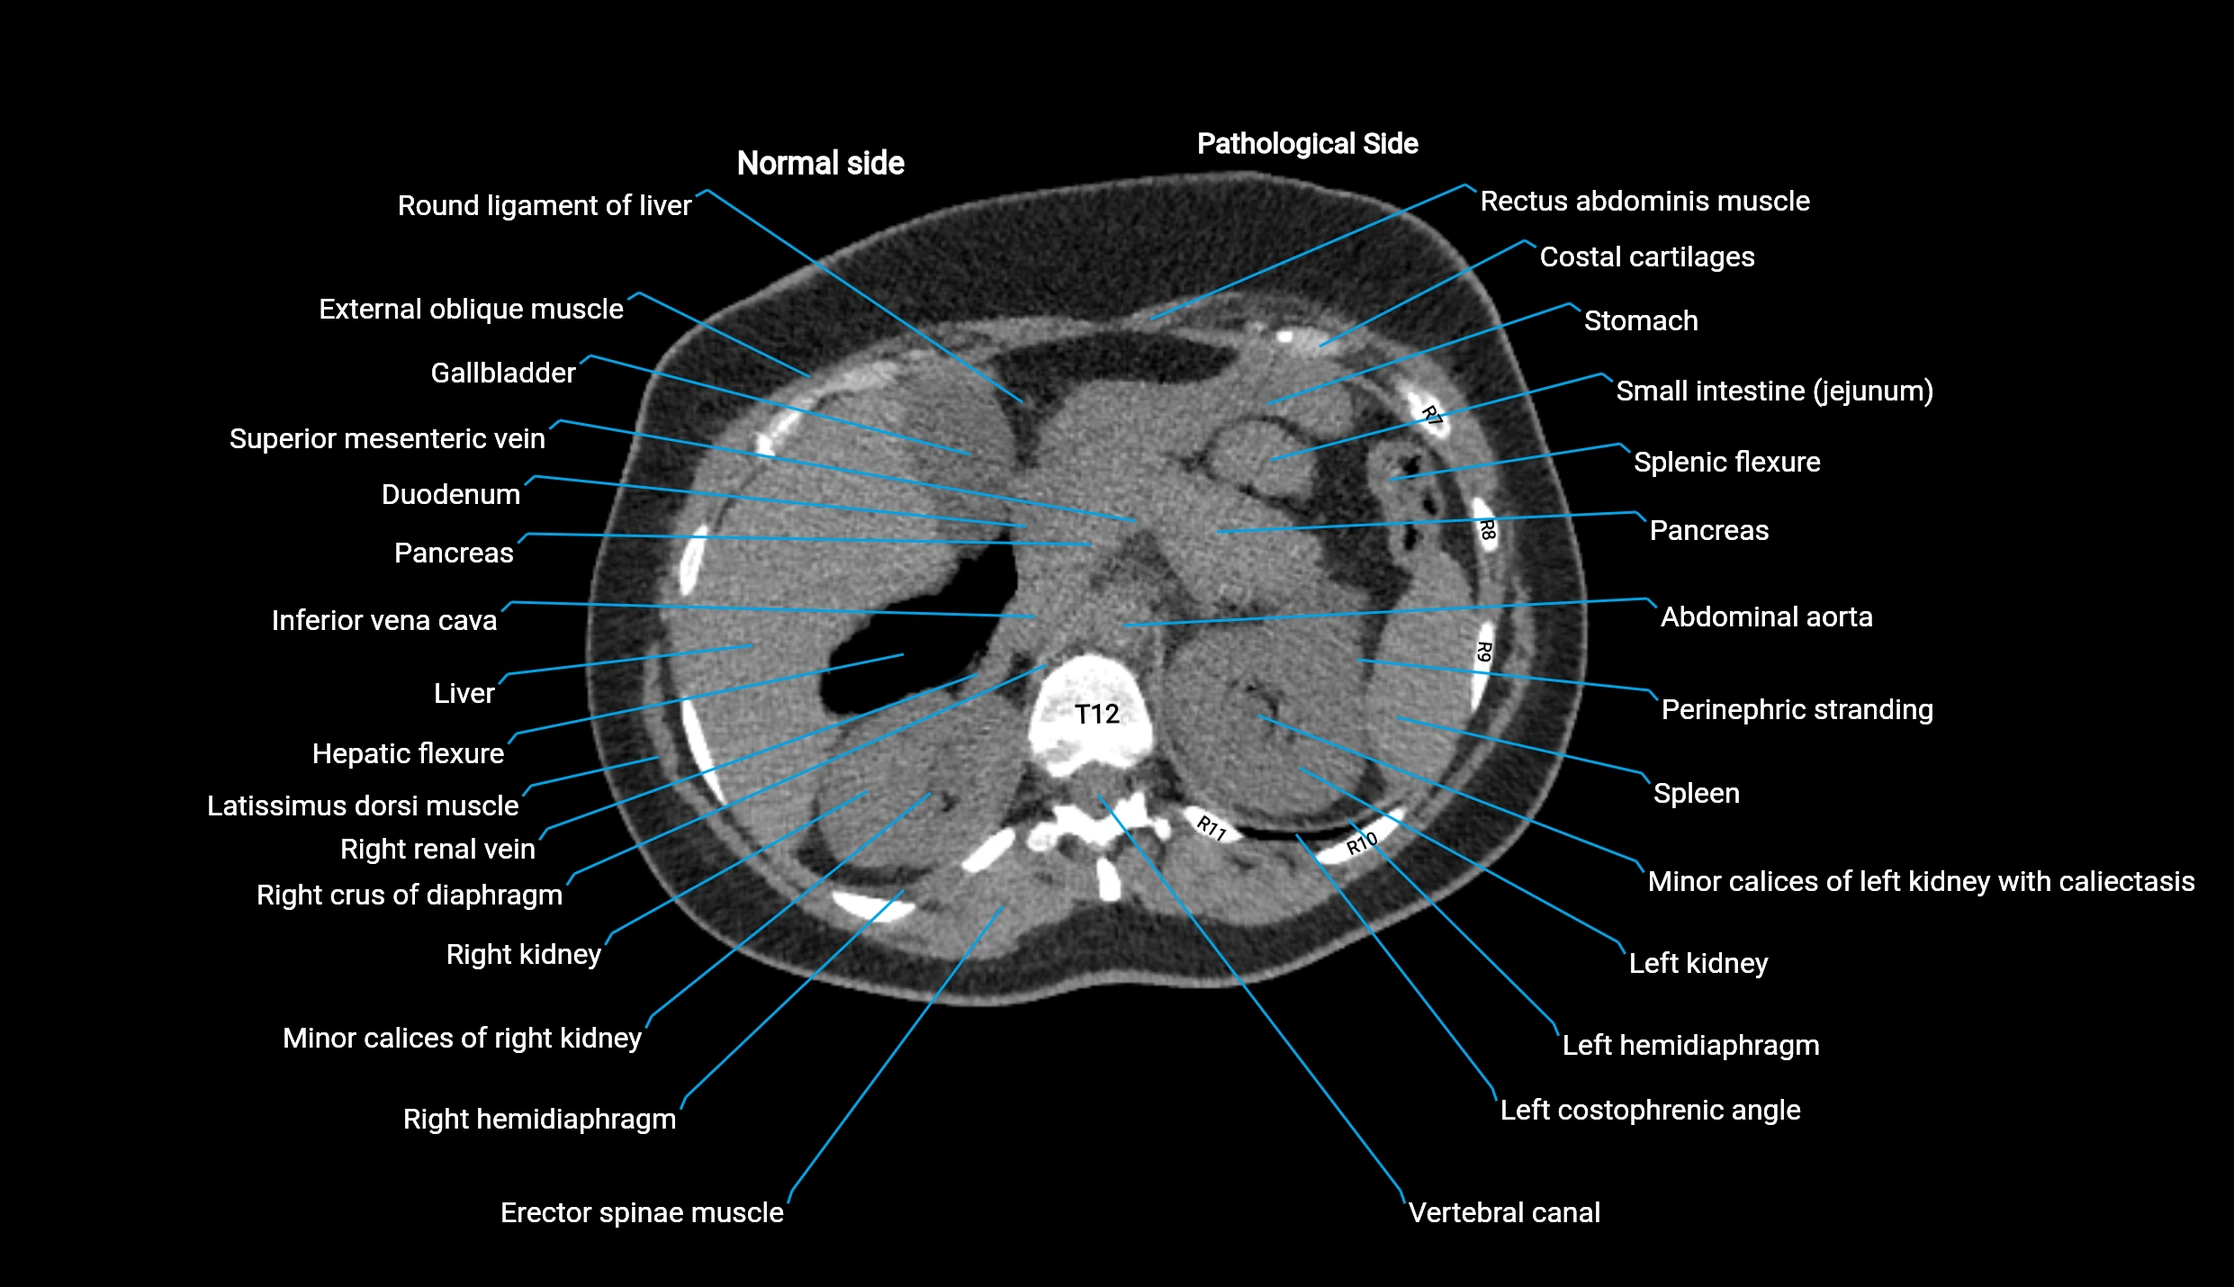

CT image

image